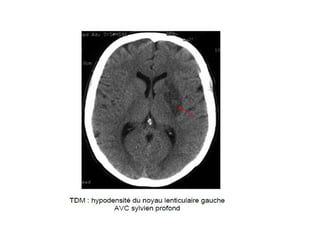

Signes précoces d’AVC ischémique (sylvien)

Signes précoces d’AVCischémique (sylvien)